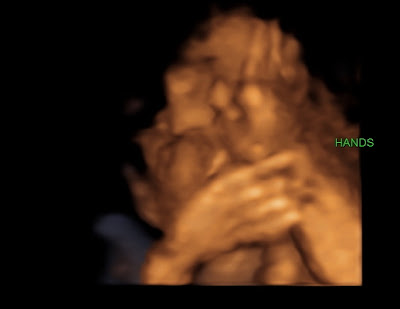

We’ve had an exciting and fun week so far. Monday, we had a 4D ultrasound done before my regular appointment. I was so excited to get a sneak peek of what Brooklyn actually looks like! She’s still got some fattening up to do, but we can tell who she’s going to look like! The consensus is that she either has my nose or my sister’s nose, so everyone has been saying she looks “just like me.” I’m horrible at looking at babies and deciding who they look like, so I’m just going with everyone else’s opinion. Guess we’ll find out soon enough anyway! During the ultrasound, Brooklyn put her thumb in her mouth, smiled several times, stretched her head back, and put her hands in front of her face. So cool! I forgot to ask how big she was, but I’m assuming she’s right around 2 lbs. Here are some of the best pictures we got. The whole time, she was nestled up close to the placenta, so we couldn’t get a great shot of her whole face, but the pictures are still good…

| Long fingers!! She got that from both of us… |